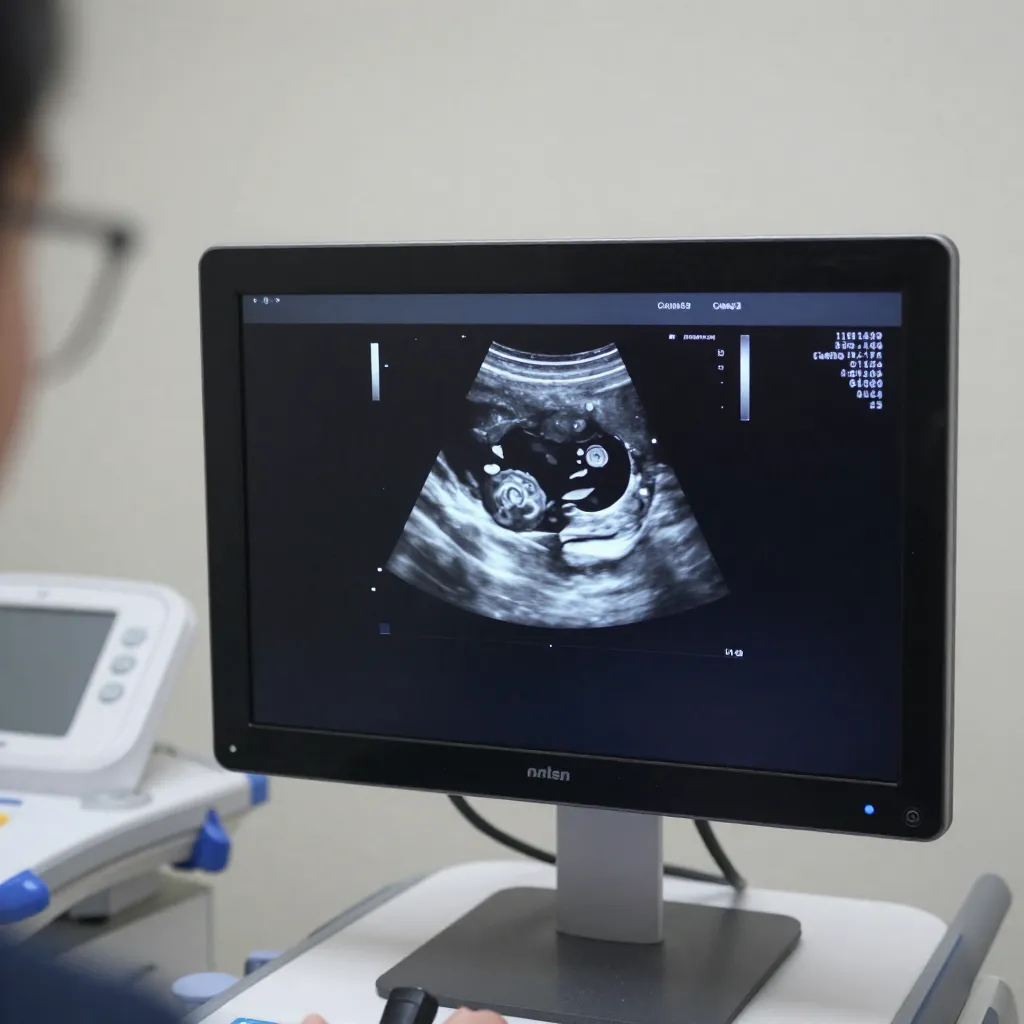

Ultrasonido Pélvico

Es el método más común para confirmar la presencia de un quiste y determinar:

- Ubicación

- Tamaño

- Composición (lleno de líquido, sólido o mixto)